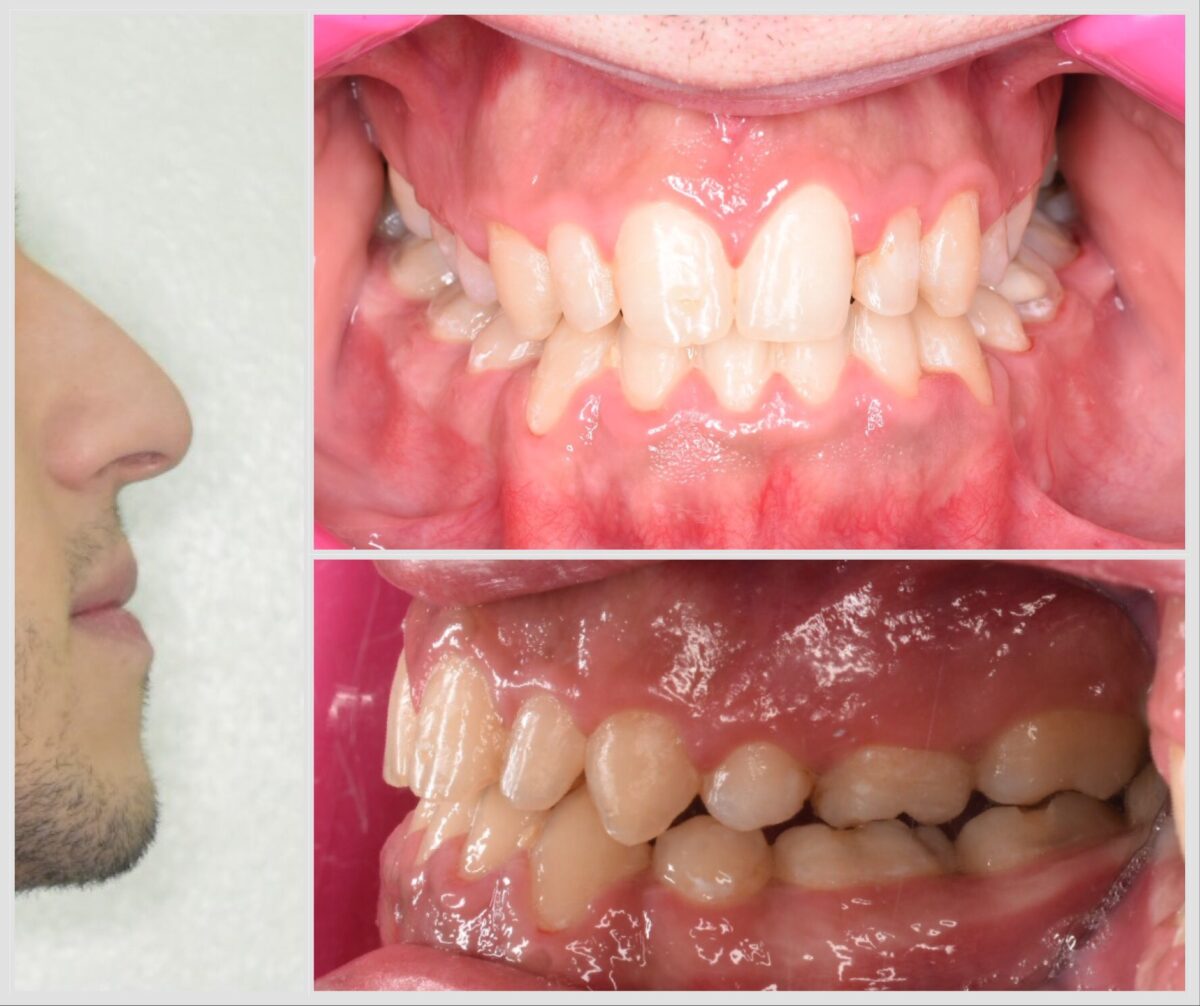

دكتور أحمد مجدي بيبدأ معاك بفحص شامل للأسنان واللثة، باستخدام أحدث الكاميرات اللي بتصور الفم من جوه وتعرض الصورة على شاشة قدامك، بحيث تشوف بنفسك المشاكل اللي محتاجة علاج. ولو الحالة تتطلب، بيعملوا أشعة بانورامية أو ثلاثية الأبعاد بتوضح أدق التفاصيل، وده بيساعد على وضع خطة علاجية دقيقة وفعالة. الأسلوب دا بيخليك شريك في قرار العلاج وفاهم كل خطوة قبل ما تبدأ.

للي محتاجين تقويم، سواء معدني أو شفاف، العيادة بتوفر أحدث حلول التقويم المناسبة لكل حالة، مع متابعة دورية لضمان تقدم العلاج بالشكل المطلوب. وكمان لو في فقدان سن، بيتم تعويضه بزرعات أسنان من التيتانيوم المعتمد دوليًا بعد فحص شامل لعظام الفك وأشعة دقيقة، لضمان أفضل ثبات ونتيجة تدوم سنين.